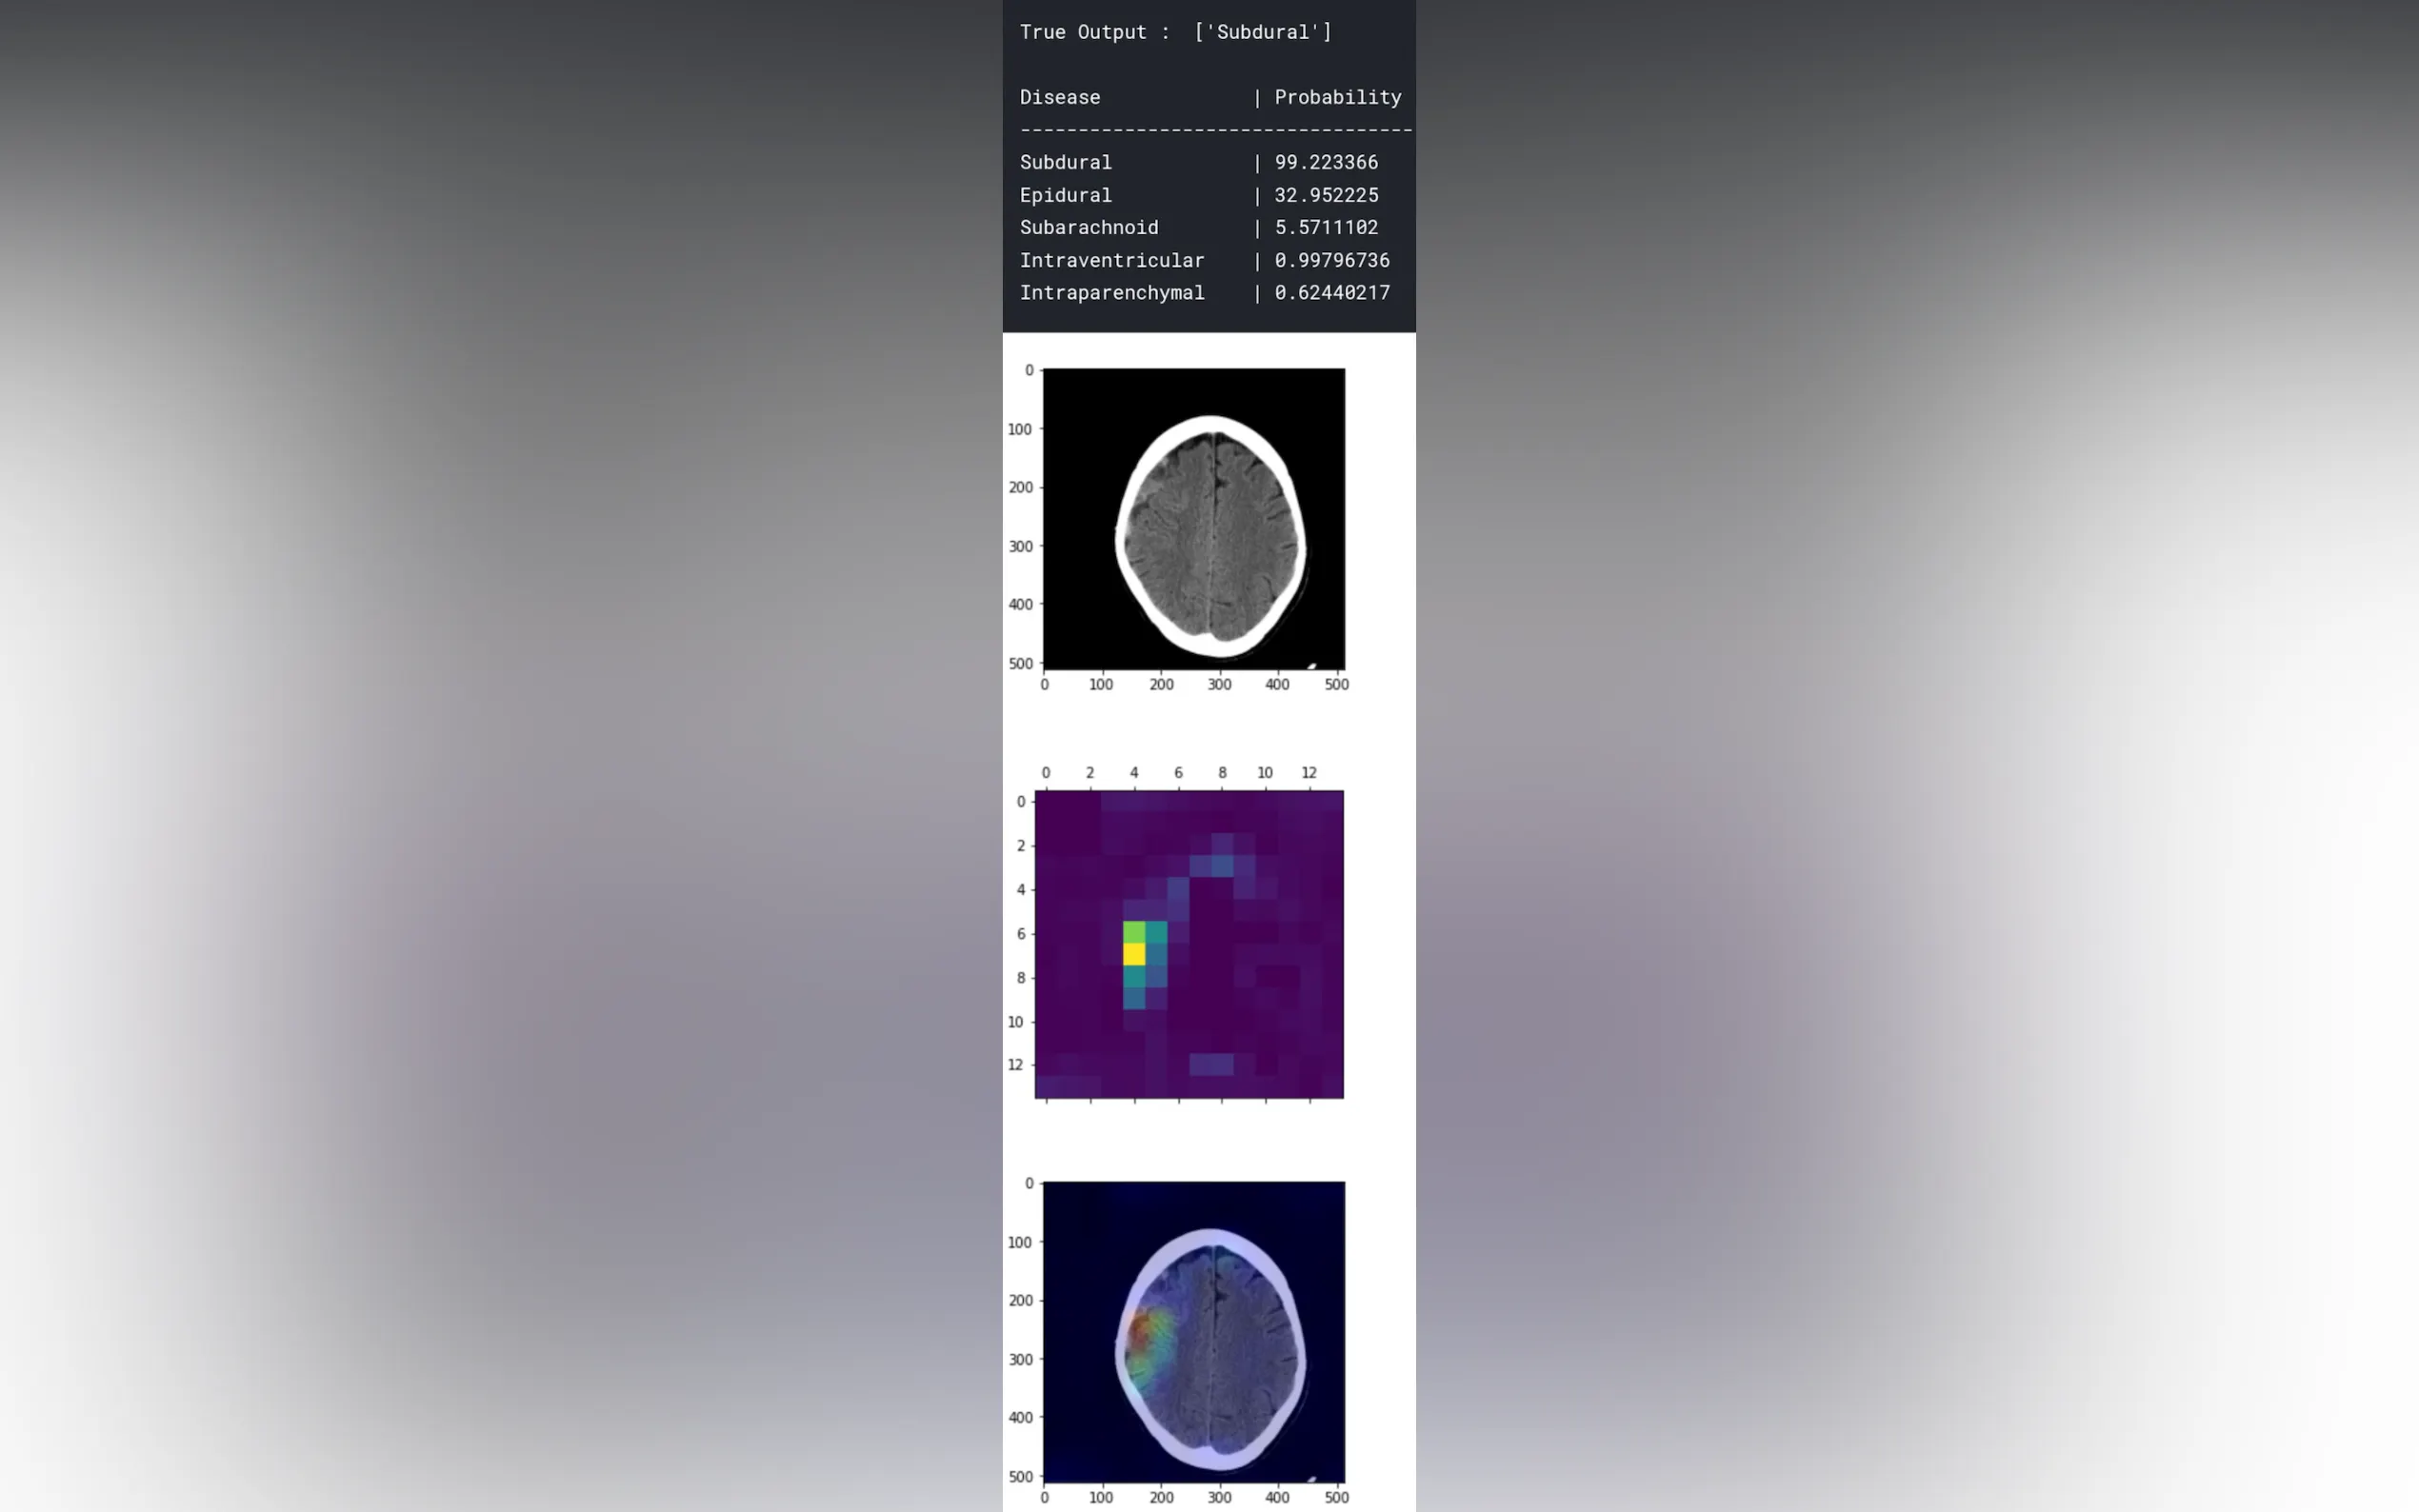

AlgoDoc is an AI-driven web app that automates disease diagnosis from X-Rays and CT scans. It uses advanced algorithms to create prediction heatmaps, making insights clear. Users get quick confirmations from verified radiologists, ensuring reliability. Healthcare professionals can speed up their diagnostic processes, resulting in faster and more accurate assessments. This tool is a must-have for modern medical practices.

- Interpretable prediction heatmaps for insights